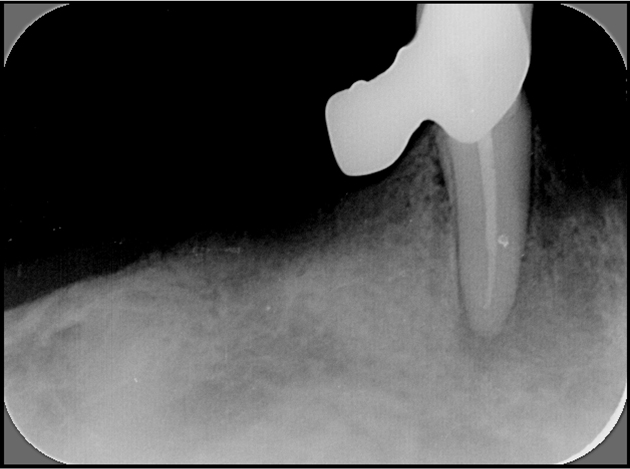

Endodonti (Kanal tedavileri,fiber post uygulamaları)